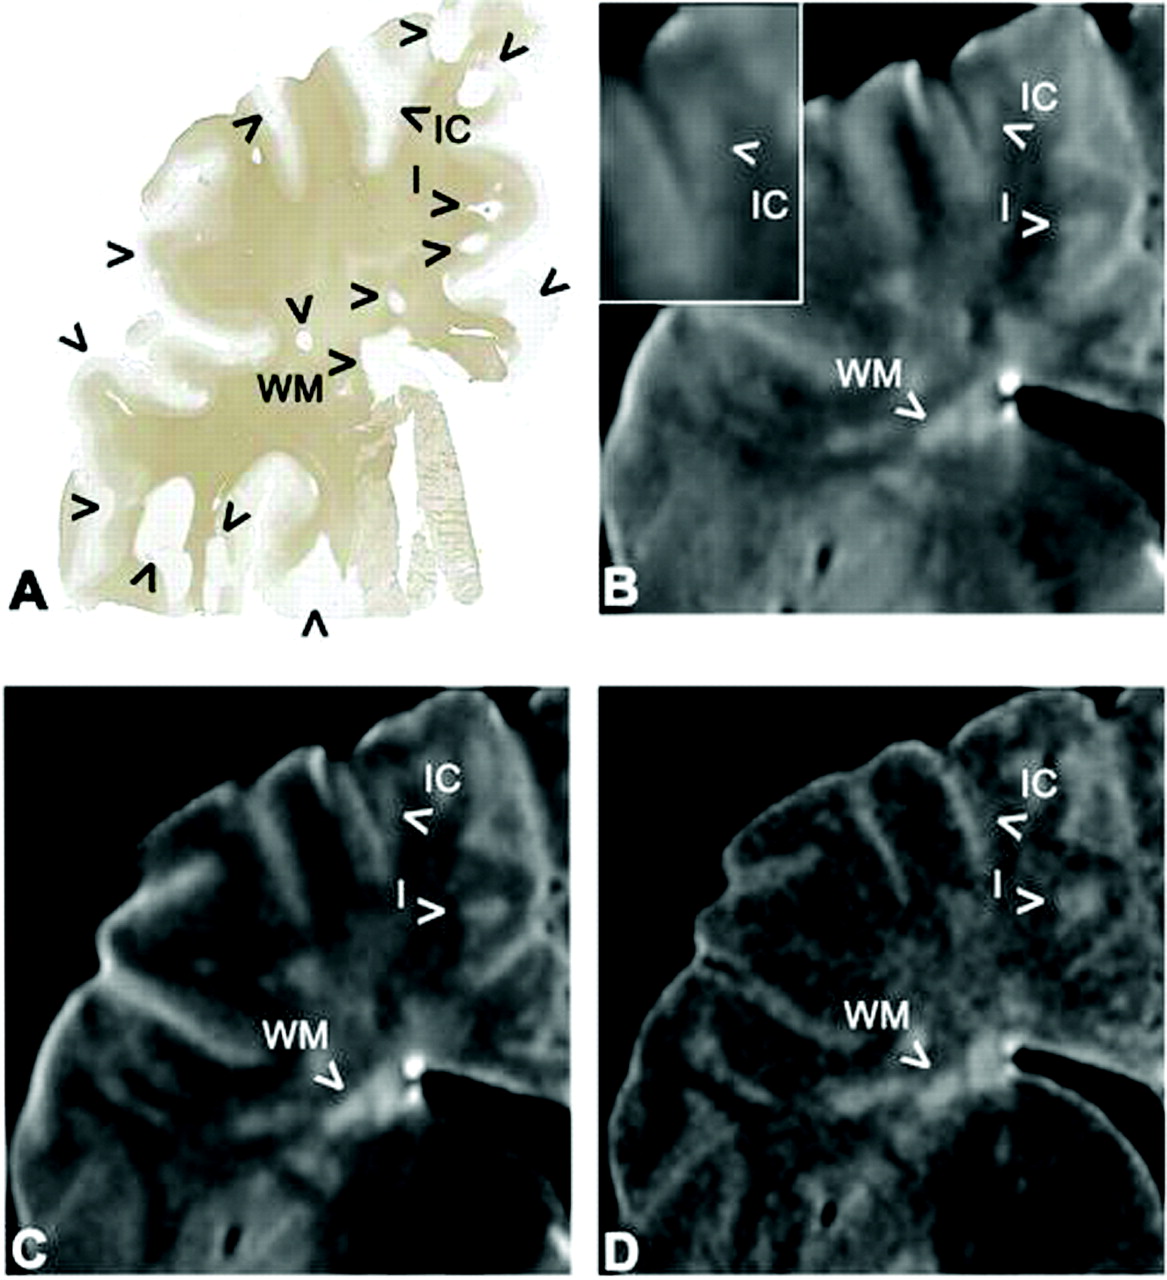

In general, MR images were well matched to the histopathologic sections (Fig 1). A total of 168 lesions were identified in the 49 tissue samples by MBP immunohistochemistry (Fig 2, Table 2): 98 GM lesions (27 type I lesions, 12 type II, 41 type III, 10 type IV, eight deep GM) and 70 WM lesions. Thus, almost equal numbers of GM lesions and WM lesions were found.

Example of a tissue sample and the matching area on postmortem MR images. WM lesions (WM), as well as type I lesions (I, mixed GM-WM), can be seen with relative ease on the different MR images. Intracortical lesions (IC) are difficult to detect and define, even in retrospect.

A, Photomicrograph (MBP immunohistochemical stain) reveals lesions (arrowheads) in the WM and cortical GM.

B, Short-echo T2-weighted SE image. Insert, a higher magnification of the intracortical lesion.

C, Long-echo T2-weighted SE image.

D, 3D FLAIR image.